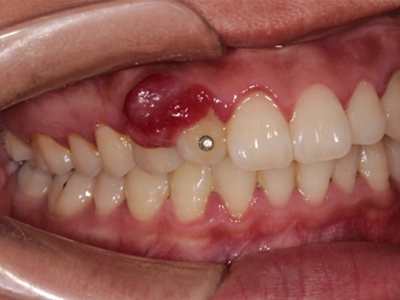

牙龈瘤是指发生在龈乳头部位的炎症反应性瘤样增生物,好发于女性,前磨牙区最为常见。牙龈瘤来源于牙周膜及牙龈的结缔组织,因其无肿瘤的生物学特征和结构,故非真性肿瘤,但切除后易复发,因此切除务必彻底,必要时拔除相关牙齿。

牙龈瘤多发于女性,以青年及中年人为常见,多发生于牙龈乳头部,位于唇、颊侧者较舌、腭侧者多,最常见的部位是前磨牙区。肿块较局限,呈圆形或椭圆形,有时呈分叶状,大小不一,直径由几毫米至数厘米。

肿块有的有蒂,如息肉状;有的无蒂,基底宽广,生长较慢,但在女性妊娠期间可能迅速增大。较大的肿块可以遮盖一部分牙及牙槽突,表面可见牙压痕,易被咬伤而发生溃疡,伴发感染。随着肿块的增长,牙槽骨壁逐渐被破坏,牙可能发生松动、移位。